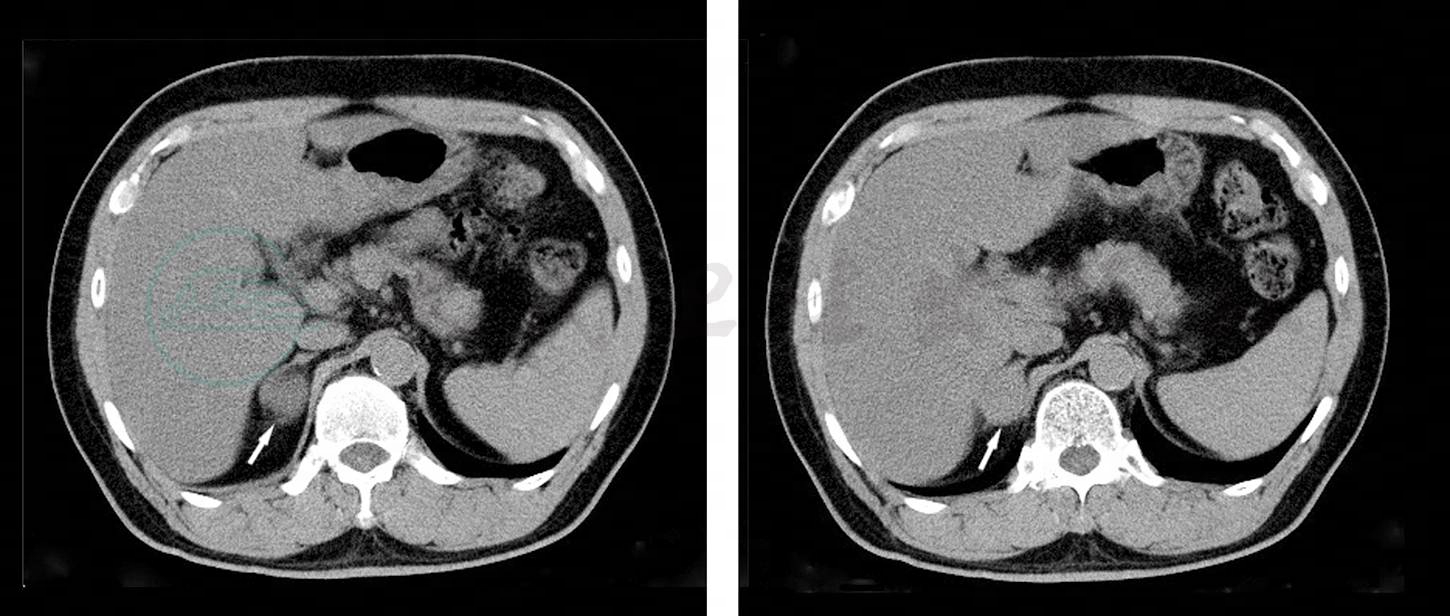

诊疗过程:入院第2天,患者小便时突发头痛、头晕,大汗淋漓,血压波动明显,发作时测量血压值为210/105mmHg,心率上升至142次/分,发作数分钟后缓解。上级医生查房,考虑到患者长期服用降压药血压控制不稳,此次出现阵发性高血压同时伴有“头痛、心悸、出汗”等症状可能为嗜铬细胞瘤释放大量儿茶酚胺入血,作用于肾上腺能受体,出现高血压的症状和体征,故不能完全排除继发性高血压的可能,遂申请泌尿外科会诊。经泌尿外科会诊后,查血浆去甲肾上腺素、血浆肾上腺素,结果回报:血浆去甲肾上腺素2579pg/ml↑(正常值参考范围:100~475pg/ml),血浆肾上腺素375pg/ml↑(正常值参考范围:30~95pg/ml)。腹部CT检查:右肾上腺后肢见一类椭圆形软组织肿块影,密度均匀,边界规整清晰,大小约为29mm×22mm×14mm,平均CT值约为37HU,周围未见淋巴结肿大影,考虑右肾上腺嗜铬细胞瘤(图1),请结合临床;脂肪肝;左肾结石或血管壁钙化。

图1 嗜铬细胞瘤